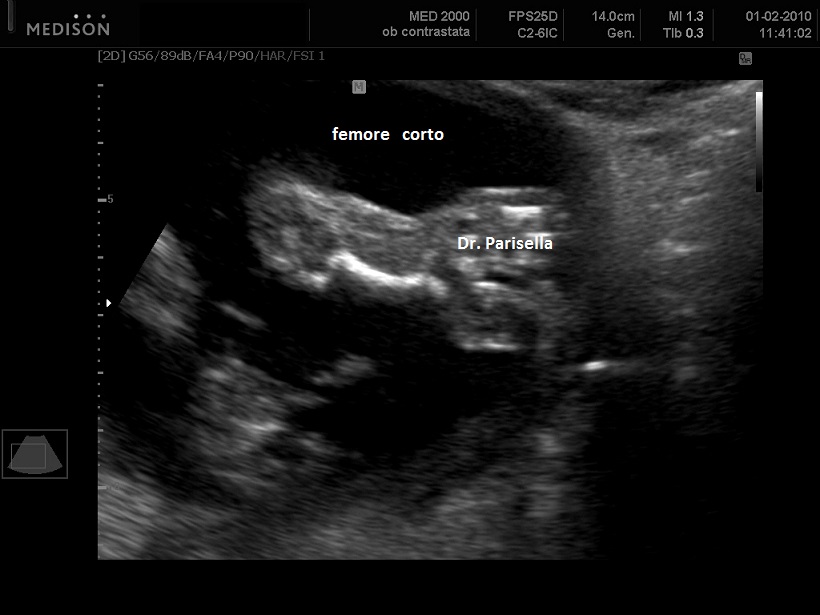

E' una malattia genetica rara caratterizzata da nanismo, palatoschisi e facies peculiare.  Il nanismo è dovuto ad ipoplasia ed incurvamento bilaterale e simmetrico del femore; il femore può essere ipoplasico o assente. La facies è caratteristica: naso corto, radice del naso allargata, micrognatia, palatoschisi, labbro superiore sottile, orecchie allungate ed inclinate posteriormente. Si osserva anche piede torto.

La diagnosi ecografica si basa su:

1) ipoplasia/aplasia femore